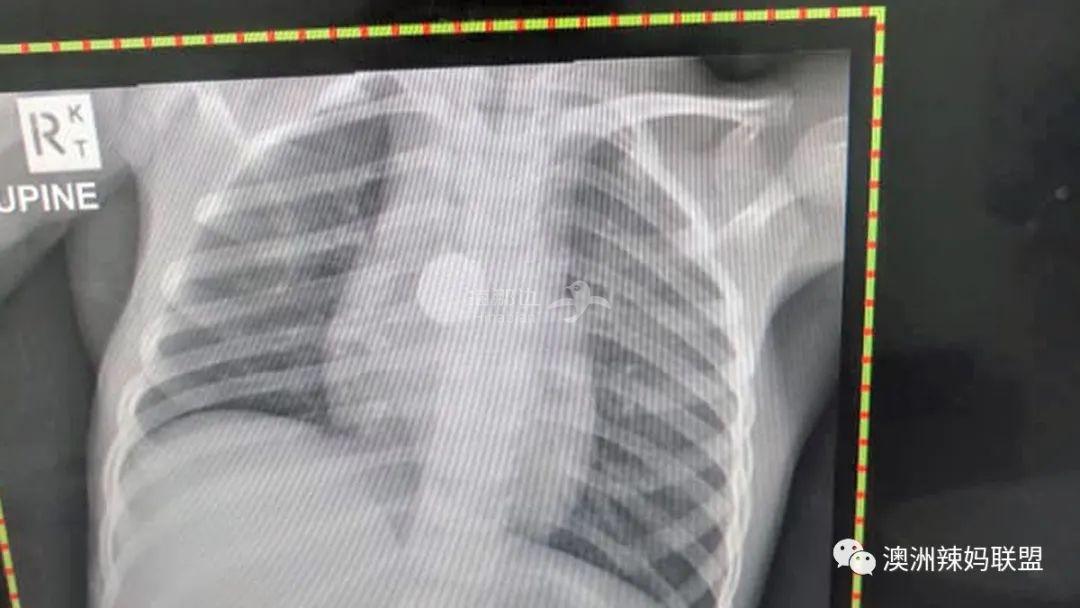

Summer马上被紧急送往布里斯班的一家医院,随后,医生通过X光发现:

Summer的食道里,

有一块2厘米长的纽扣电池!

这块纽扣电池卡在Summer的食道中,

对唾液产生反应,

反复在组织中灼烧,

把主动脉烧出了一个洞!